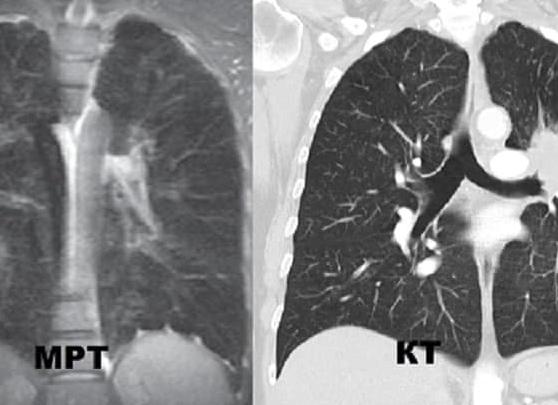

Это томограммы легких. Слева МРТ, в справа КТ. Контрастность и чёткость изображения справа существенно лучше.